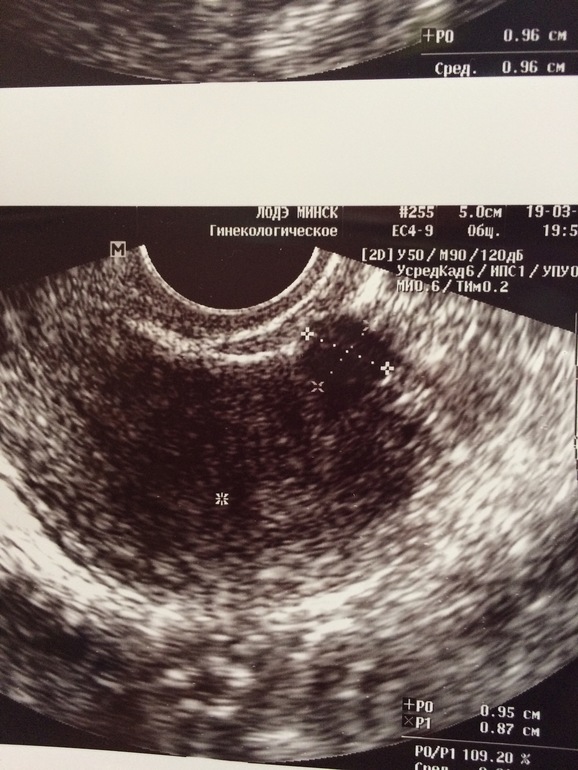

27дц хгч 28,57; 28дц хгч 14+ сделала УЗИ сказали миома-фото прилагаю

Спасибо! Просто я почему то засомневалась везде в нэте миома выглядит как белый сгусток, а у меня черный шарик!

Выше написано что хгч на 27дц-28,5 , а на 28 дц - 14; вот я и побежала на УЗИ а мне стрелочками показали , что это миома;((

Лаборатории разные и второй раз сдавала не натощак((( но нормы лабораторий одинаковые , так на УЗИ крестиками пометили миому (((желтое тело 12мм

Написали 0,95 см, сказали маленькая тоже не трогать, просто я очень расстроилась пол года назад все хорошо было, а тут первый цикл планирования и такое....